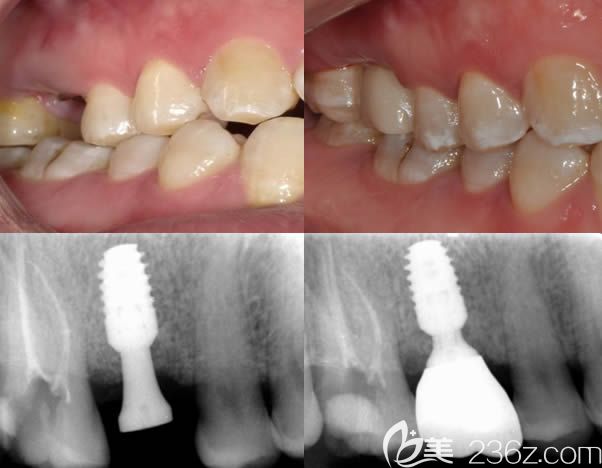

北京牙管家口腔波医师美学种植牙案例赏析:

顾客反馈:我是活动时定的项目,价格折扣很大,但是刘院长还是挺负责的,种牙过程中对我的疑问讲的也很详细,也没有额外的收费。另外,种牙过程没有太大不适,就是在牙槽骨打孔时候有点酸痛,但刚有感觉就结束了,很快!麻醉过劲之后有一定疼痛,但可以忍受,整体感觉还是很满意的。